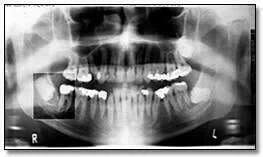

Hình ảnh thể hiện mức độ tiếp xúc quá mức có thể dẫn đến việc không phát hiện được các đặc điểm bệnh lý. Hình 34a là phiên bản nâng cao kỹ thuật số của bức ảnh 34b. Có thể thấy Hình 34b bị phơi sáng quá mức khi chụp, thể hiện rõ ràng sự xuất hiện của một vùng bức xạ gây ra sự mở rộng và mỏng đi của phần xương bên dưới của hàm phải – những đặc điểm không thể hiện rõ trên bản gốc.

Hình ảnh với liều tia không đủ có thể dẫn đến không phát hiện được các đặc điểm bệnh lý. Hình 35a là một phiên bản nâng cao kỹ thuật số. Chúng ta có thể dễ dàng thấy chiếc răng hàm thứ ba bên phải bị tác động mà bị mờ đi trên bản gốc. Sự tăng cường này cũng chứng tỏ rõ ràng bệnh nhân có một bệnh lý liên quan đến răng hàm dưới thứ hai bên phải.